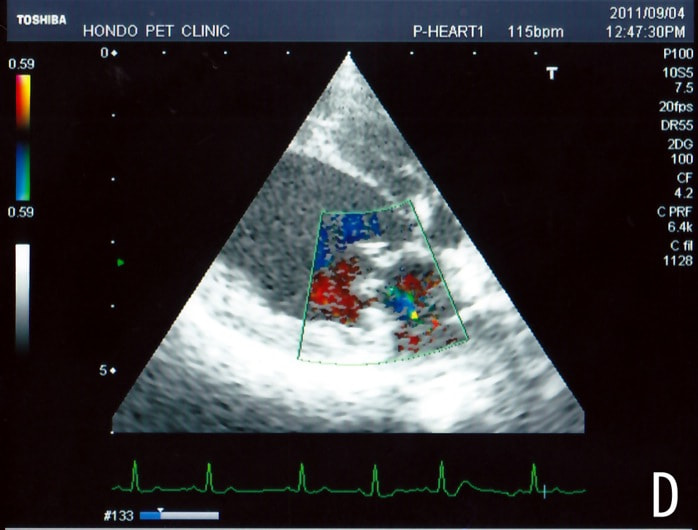

C:超音波画像 肺動脈領域の異常血流

D:左心系の拡張による二次的僧帽弁逆流

左側胸壁よりLevine 4/6の連続性心雑音が聴取された。胸部レントゲン検査において心拡大が認められ、超音波検査においても肺動脈領域に連続的な異常血流が観察された。大学病院を紹介受診され、手術が行われた。現在はACE阻害薬のみの内服で補助的治療を行っている。